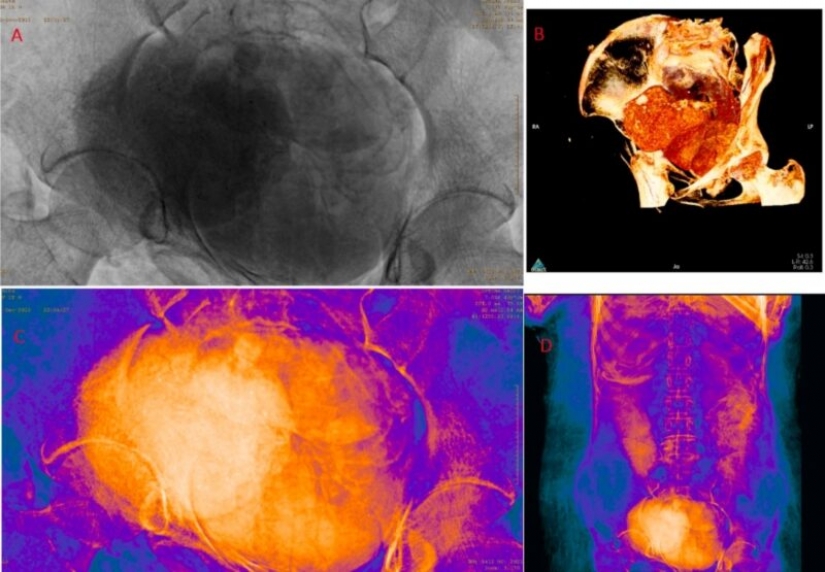

For the new study, scientists decided to scan the body and were surprised to find that in fact, a woman in the seventh month of pregnancy is lying in the coffin.

According to scientists, this is the only known case of a well-preserved pregnant Egyptian mummy. They determined that the woman was between 20 and 30 years old. And the size of the fetal skull suggests that she was somewhere between 26 and 28 weeks pregnant.